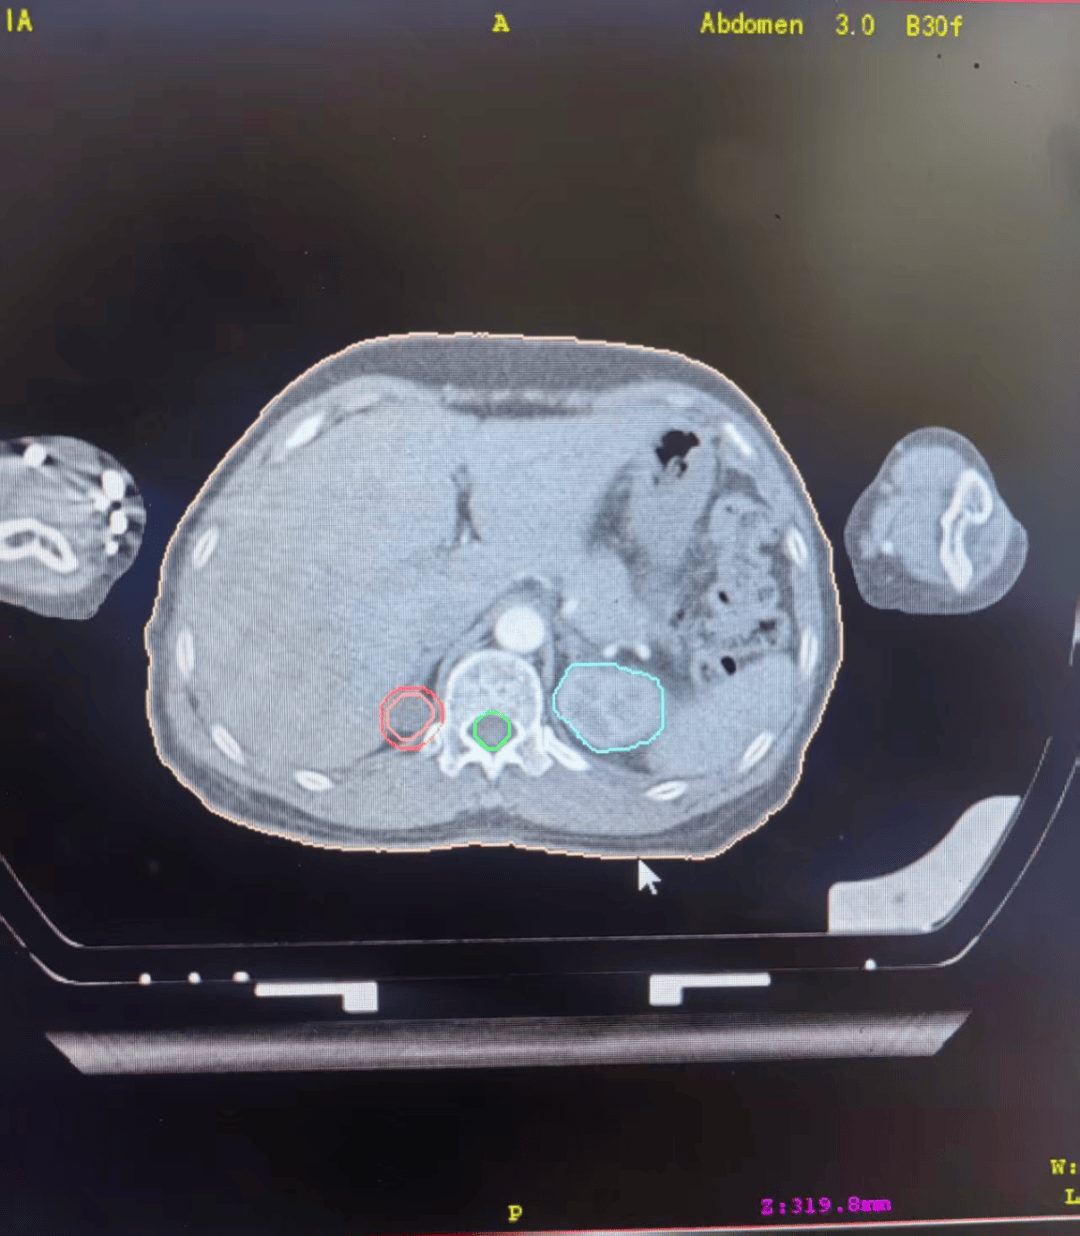

13年前,这位女士在检查中被确诊肺癌晚期,伴肾上腺转移。

利用陀螺刀技术精准聚焦病灶,对肺部原发灶与肾上腺转移灶进行精准治疗,在高效杀伤肿瘤细胞的同时,最大程度保护正常组织,减少身体损伤。

定期复查显示原发部位肿瘤无明显进展